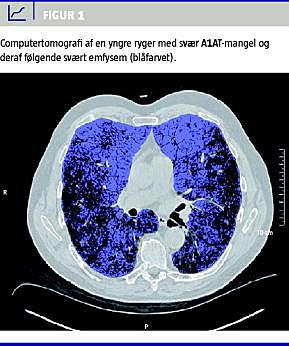

Alfa1 -antitrypsin (A1AT)-mangel er en medfødt og arvelig proteindefekt, som disponerer til leversygdom og til udvikling af kronisk obstruktiv lungesygdom (KOL) hos voksne rygere. A1AT dannes i leveren. Stoffet hæmmer elastase og andre proteolytiske enzymer, som dannes i forbindelse med betændelsesreaktioner. Tobaksrygning medfører en kronisk betændelse i lunger og luftveje med influks af bl.a. neutrofile granulocytter, som frisætter elastase o.l. Ved A1AT-mangel mener man, at elastasens nedbrydning af lungevævet ikke hæmmes tilstrækkeligt, hvilket fører til emfysem og KOL [1], som det fremgår af Figur 1 .